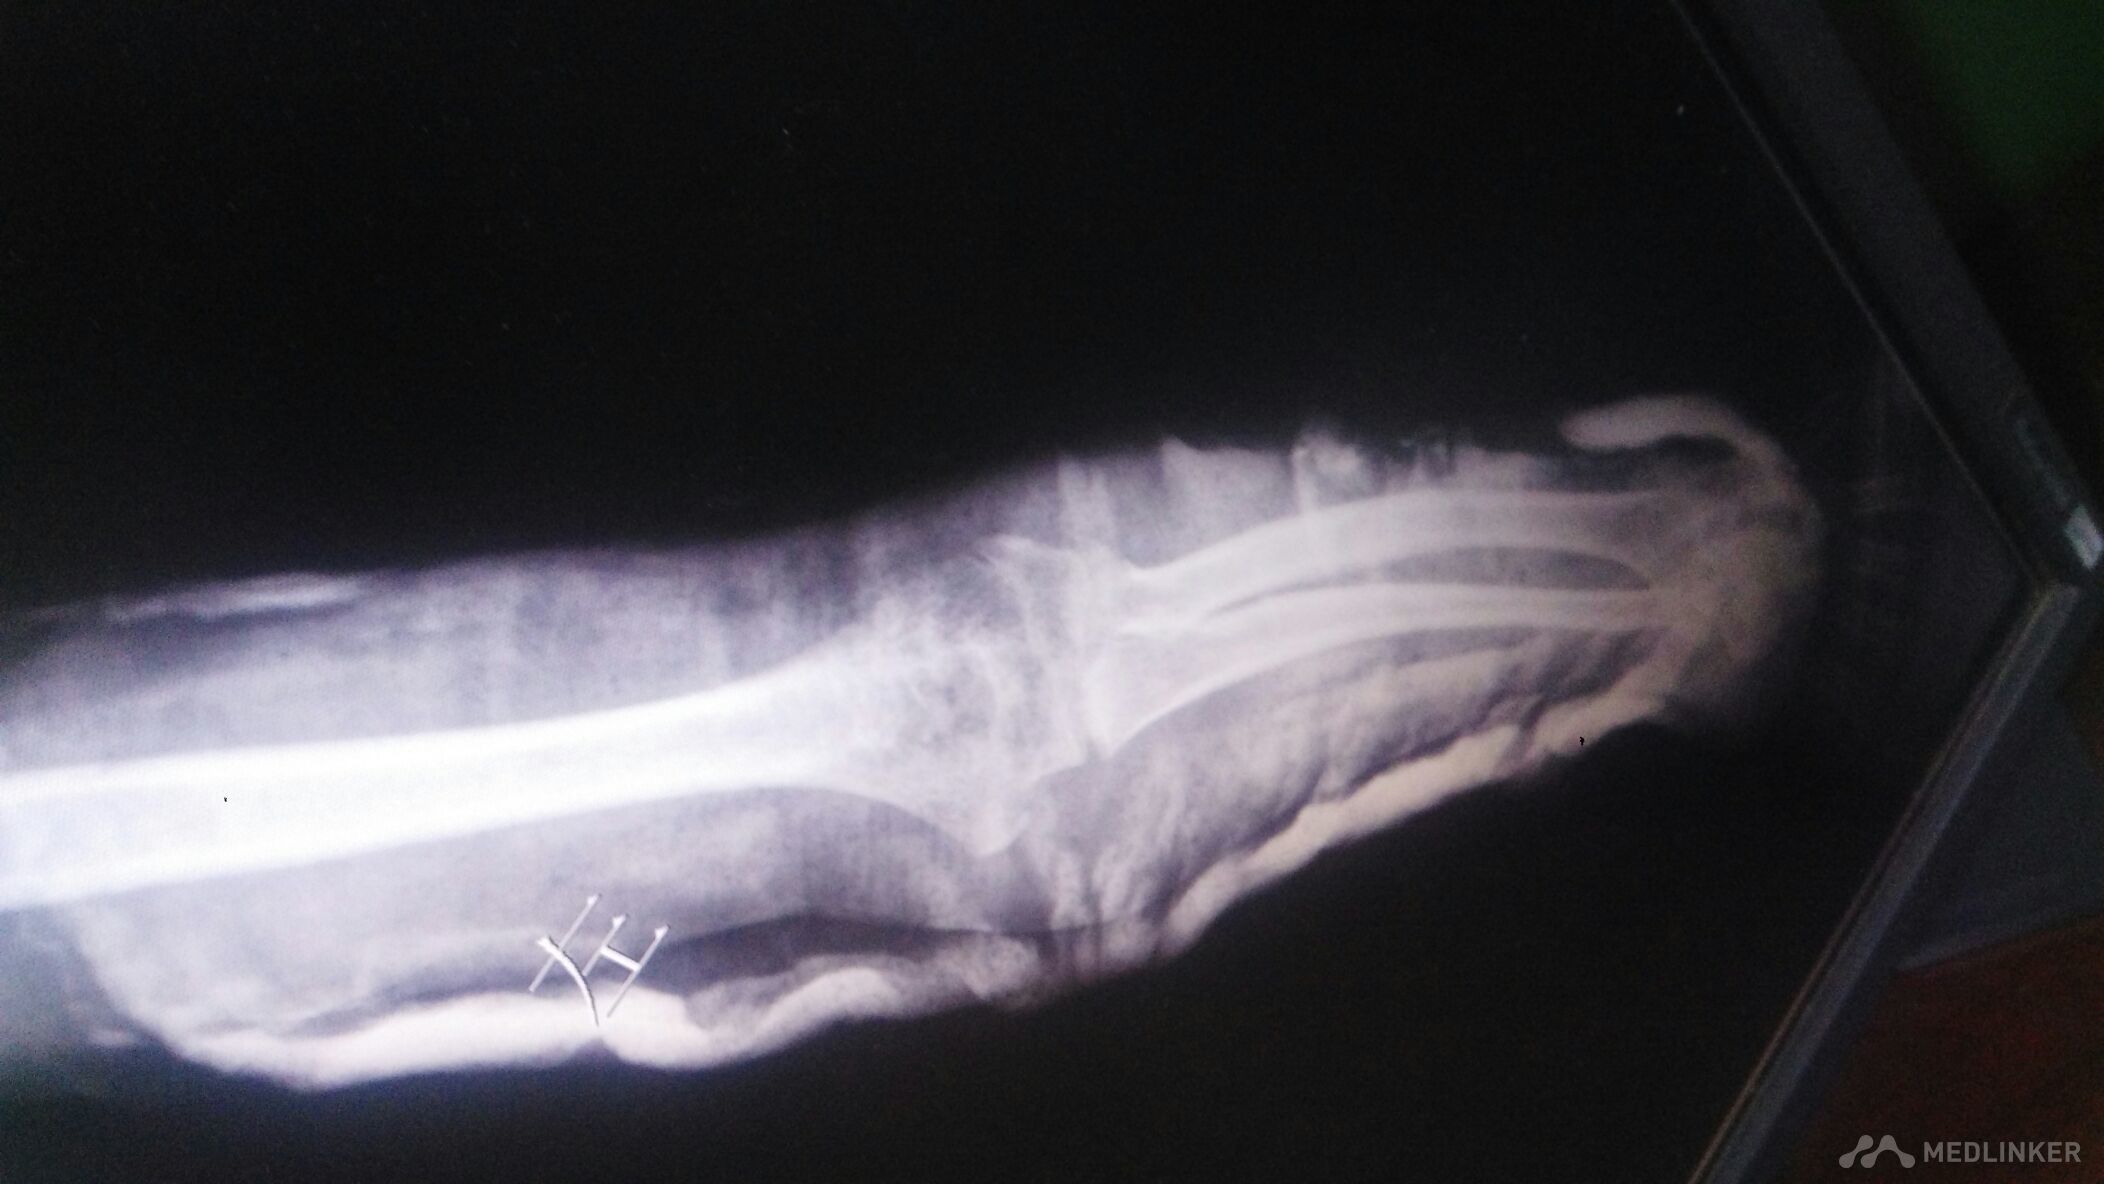

外伤后儿童的肘关节脱位。

左肘部肿痛畸形。以尺骨鹰嘴处为著,压痛阳性,叩痛阳性。左肘部活动受限。

骑自行车时摔倒致左肘部肿痛1小时。左肘部肿痛,畸形。活动受限。左手麻木。

左肘部脱位,后脱位,可以保守治疗。

肘关节肿胀明显。畸形明显。虽然脱位,韧带也有损伤。恢复有一定的时间。